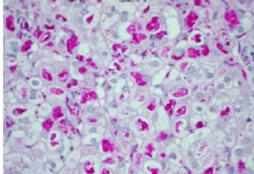

Anatomopatologia: Il fegato di un bambino affetto da tirosinemia va incontro ad una cirrosi micro o macronodulare. I noduli in verde sono dei noduli cirrotici.